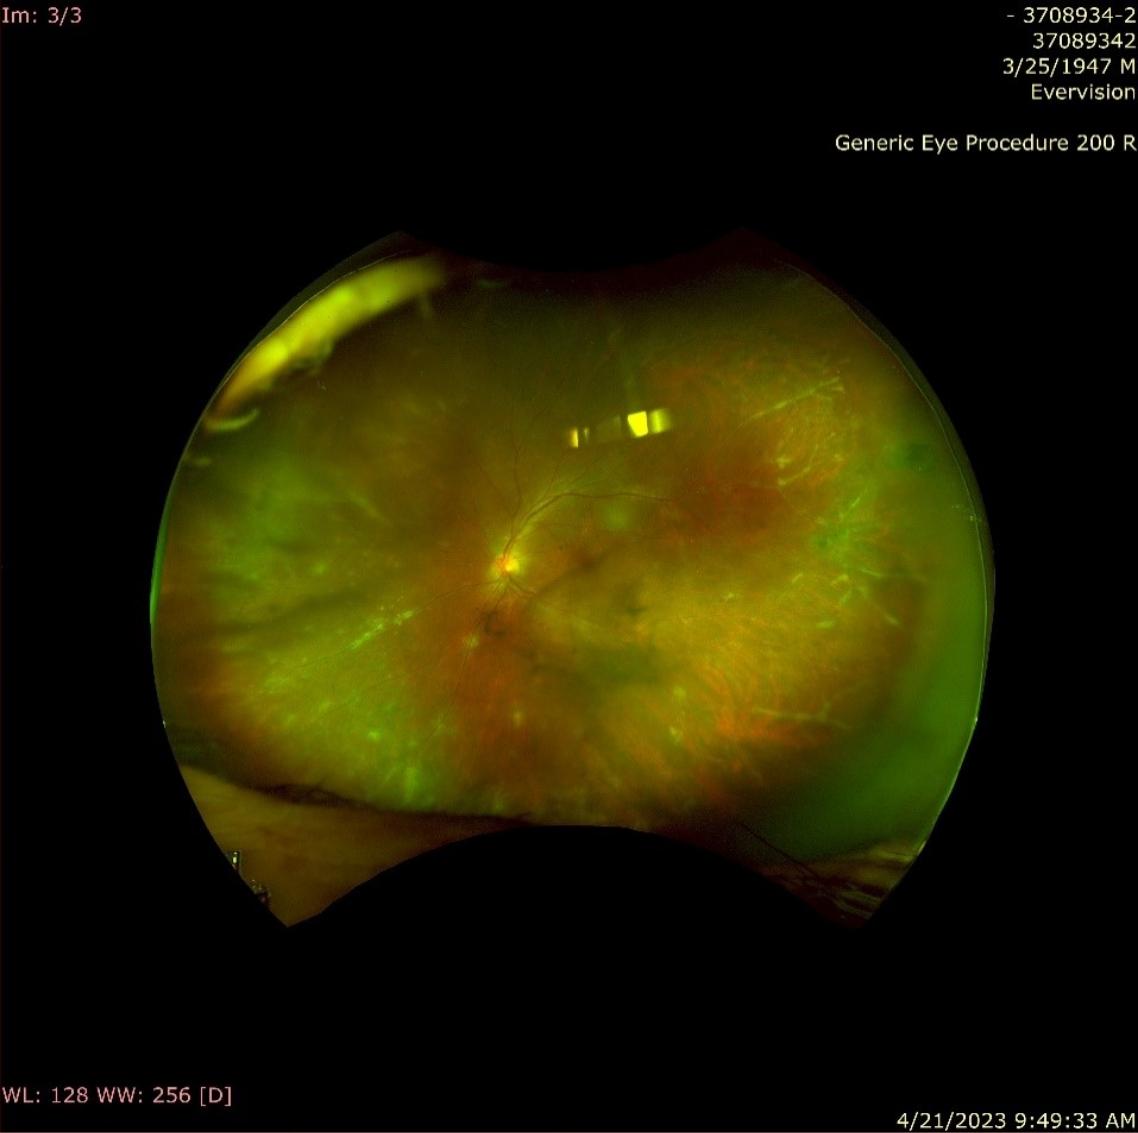

朱女士視力檢查結果發現右眼視力還有0.8,但左眼視力只剩0.3;「雙眼有輕微初期白內障,及雙眼後葡萄膜炎,合併黃斑病變及嚴重漿液性視網膜剝離,詳細檢查發現為免疫療法藥物誘發非感染性葡萄膜炎的罕見病徵。」

黃德光表示,「眼科醫師經過精密的儀器和散瞳檢查後,可以根據檢查結果,譬如角膜內皮上聚集許多沉澱物,眼內的發炎細胞增加,視網膜和脈絡膜產生病灶,就可確診葡萄膜炎。」

黃德光指出,癌症治療中最擔心的,莫過於腫瘤自己產生的葡萄膜炎。「臨床上有時能看到身體的惡性腫瘤或血液腫瘤轉移到眼內,這時檢查可能可以看到脈絡膜或葡萄膜腫塊、視網膜下細胞浸潤、或玻璃體內不正常的白血球浸潤;少部分病人因腫瘤本身引發的自體免疫反應攻擊視網膜細胞,可能會造成特殊的視網膜病變。」因此黃德光表示,發現癌症病人有葡萄膜炎時,應先審視全身腫瘤控制的情況,是否有其他地方的轉移,並針對惡性腫瘤本身加以治療。

「患者的葡萄膜炎表徵千變萬化,有些只有些微發炎細胞增加,有些產生比較嚴重的脈絡膜發炎。所幸這種癌症治療藥物所引發的葡萄膜炎,相較於前兩者,較沒有重大的生命危險,只要針對發炎加以治療,輕微時使用眼藥水,嚴重時暫停使用免疫療法並加上身體消炎藥物或眼內注射,即有可能讓發炎緩解消除,讓病患恢復視力。」